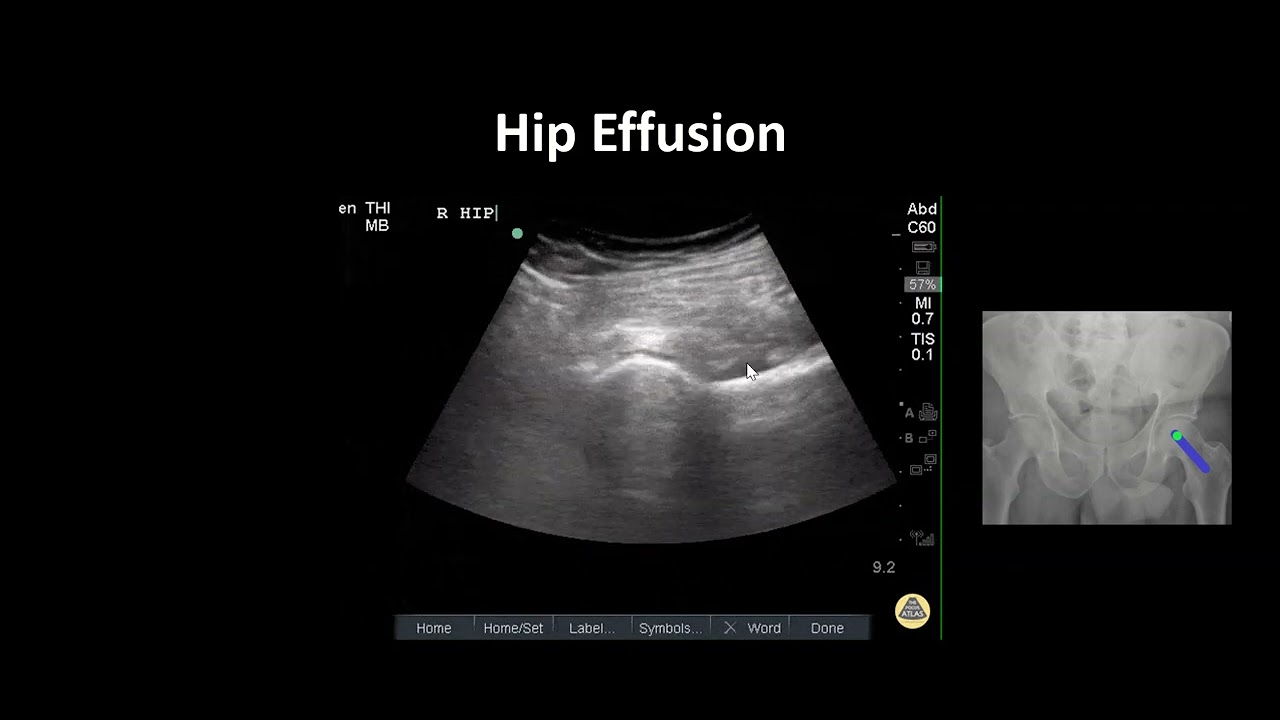

Hip Effusion

Описание: In this video Dr. Nhu Nguyen Le discusses how to identify a hip effusion in a patient with a suspected septic joint.